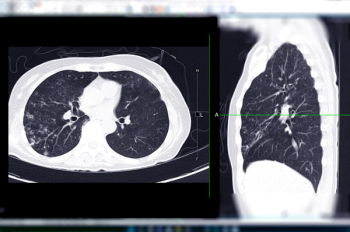

In the newly released Lung-RADS 2022 classification system for computed tomography (CT) lung cancer screening, the American College of Radiology (ACR) has noted a variety of updates including new classification criteria for atypical pulmonary cysts and airway nodules, time intervals for nodule growth and a new stepped management approach for Lung-RADS categories 3 and 4A.